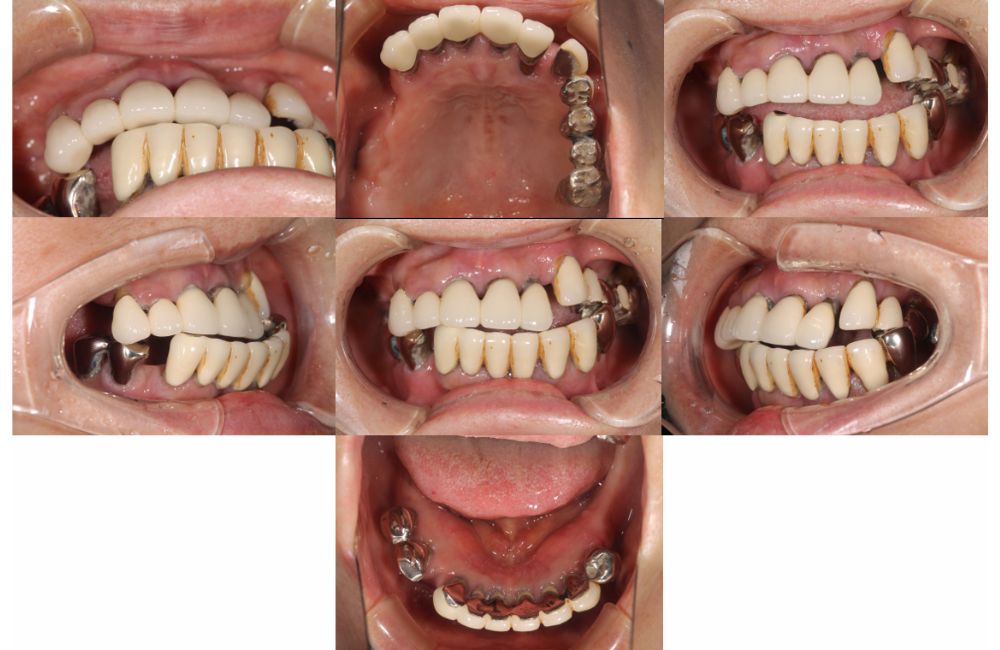

初診時の口腔内写真

患者様は「左上のブリッジが外れかけている、歯がないところに歯を入れたい」という主訴で来院しました。

診断の結果、骨格の問題や個々の歯の問題から、残念ながらすべての歯を抜歯せざるを得ない状況でした。

しっかり噛みたいという希望に沿うために、上は総義歯、下はインプラントオーバーデンチャー

(インプラントを使い、それを支えに入れ歯を入れること)で治療することとなりました。